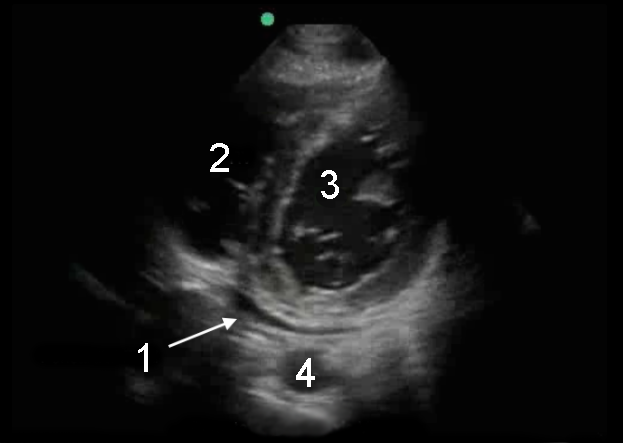

心胸骨傍短軸(PSAX)胸水画像

心嚢液 (液)

右心室 (RV)

左心室(LV)

大動脈 (Ao)